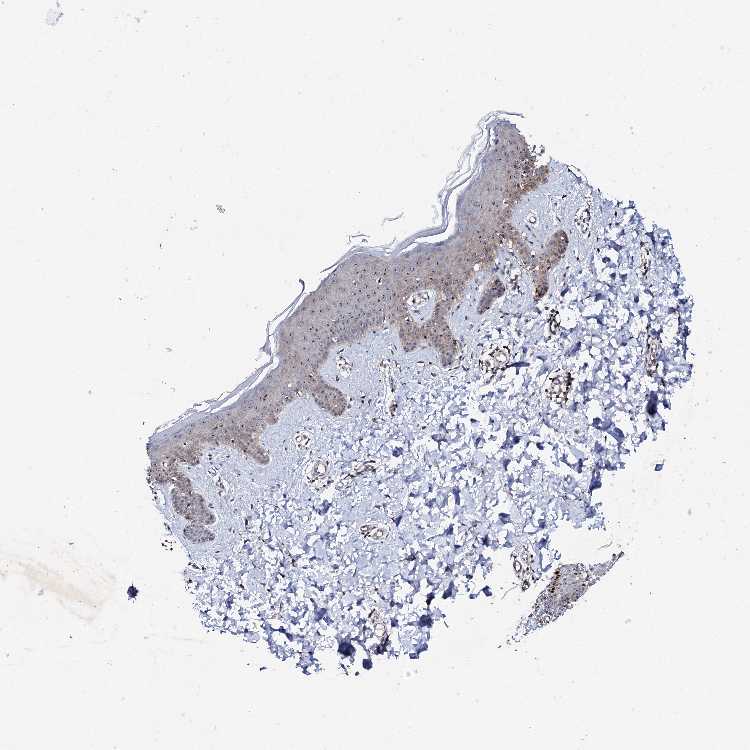

SKIN 1 - Antibody stainingi

Antibody staining in the annotated cell types in the current human tissue is reported as not detected, low, medium, or high, based on conventional immunohistochemistry profiling in selected tissues. This score is based on the combination of the staining intensity and fraction of stained cells.

Each image is clickable and will lead to virtual microscopy that enables deeper exploration of all samples and also displays staining intensity scores, fraction scores and subcellular localization as well as patient and tissue information for each sample.

Antibody HPA039618

Langerhans Medium

Fibroblasts Medium

Keratinocytes Medium

Melanocytes Medium